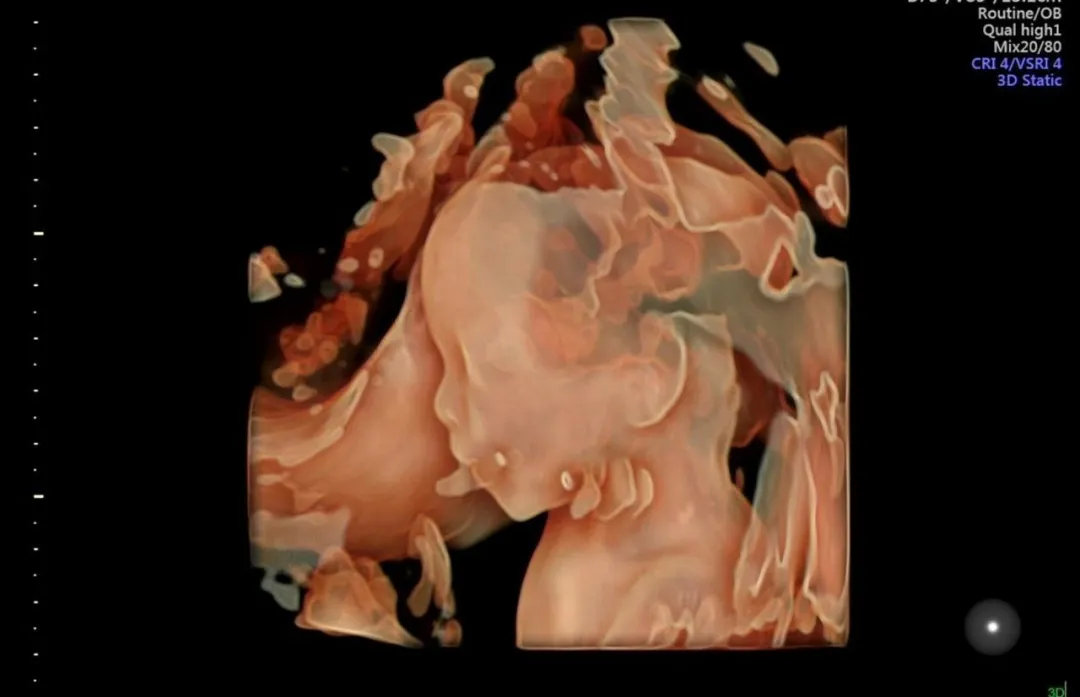

22-26周时,宝妈们就可以去做四维彩超,通过四维彩超看见宝宝的动态影像,甚至看到宝宝的手脚、宝宝的面部大概轮廓以及他们的表情动作。

一些活泼的宝宝也在这里提前向爸爸妈妈们展示了自己的幽默细胞,不信,你看:

专注地看着哪里呢

想知道宝宝在肚子里干什么,最直观的办法就是通过四维彩超。四维彩超不仅能让孕妈看到宝宝的样子,也是孕期检查相当重要的一环,能筛查胎儿各项器官的发育情况,为先天性体表畸形和先天性心脏病的筛查提供科学依据。